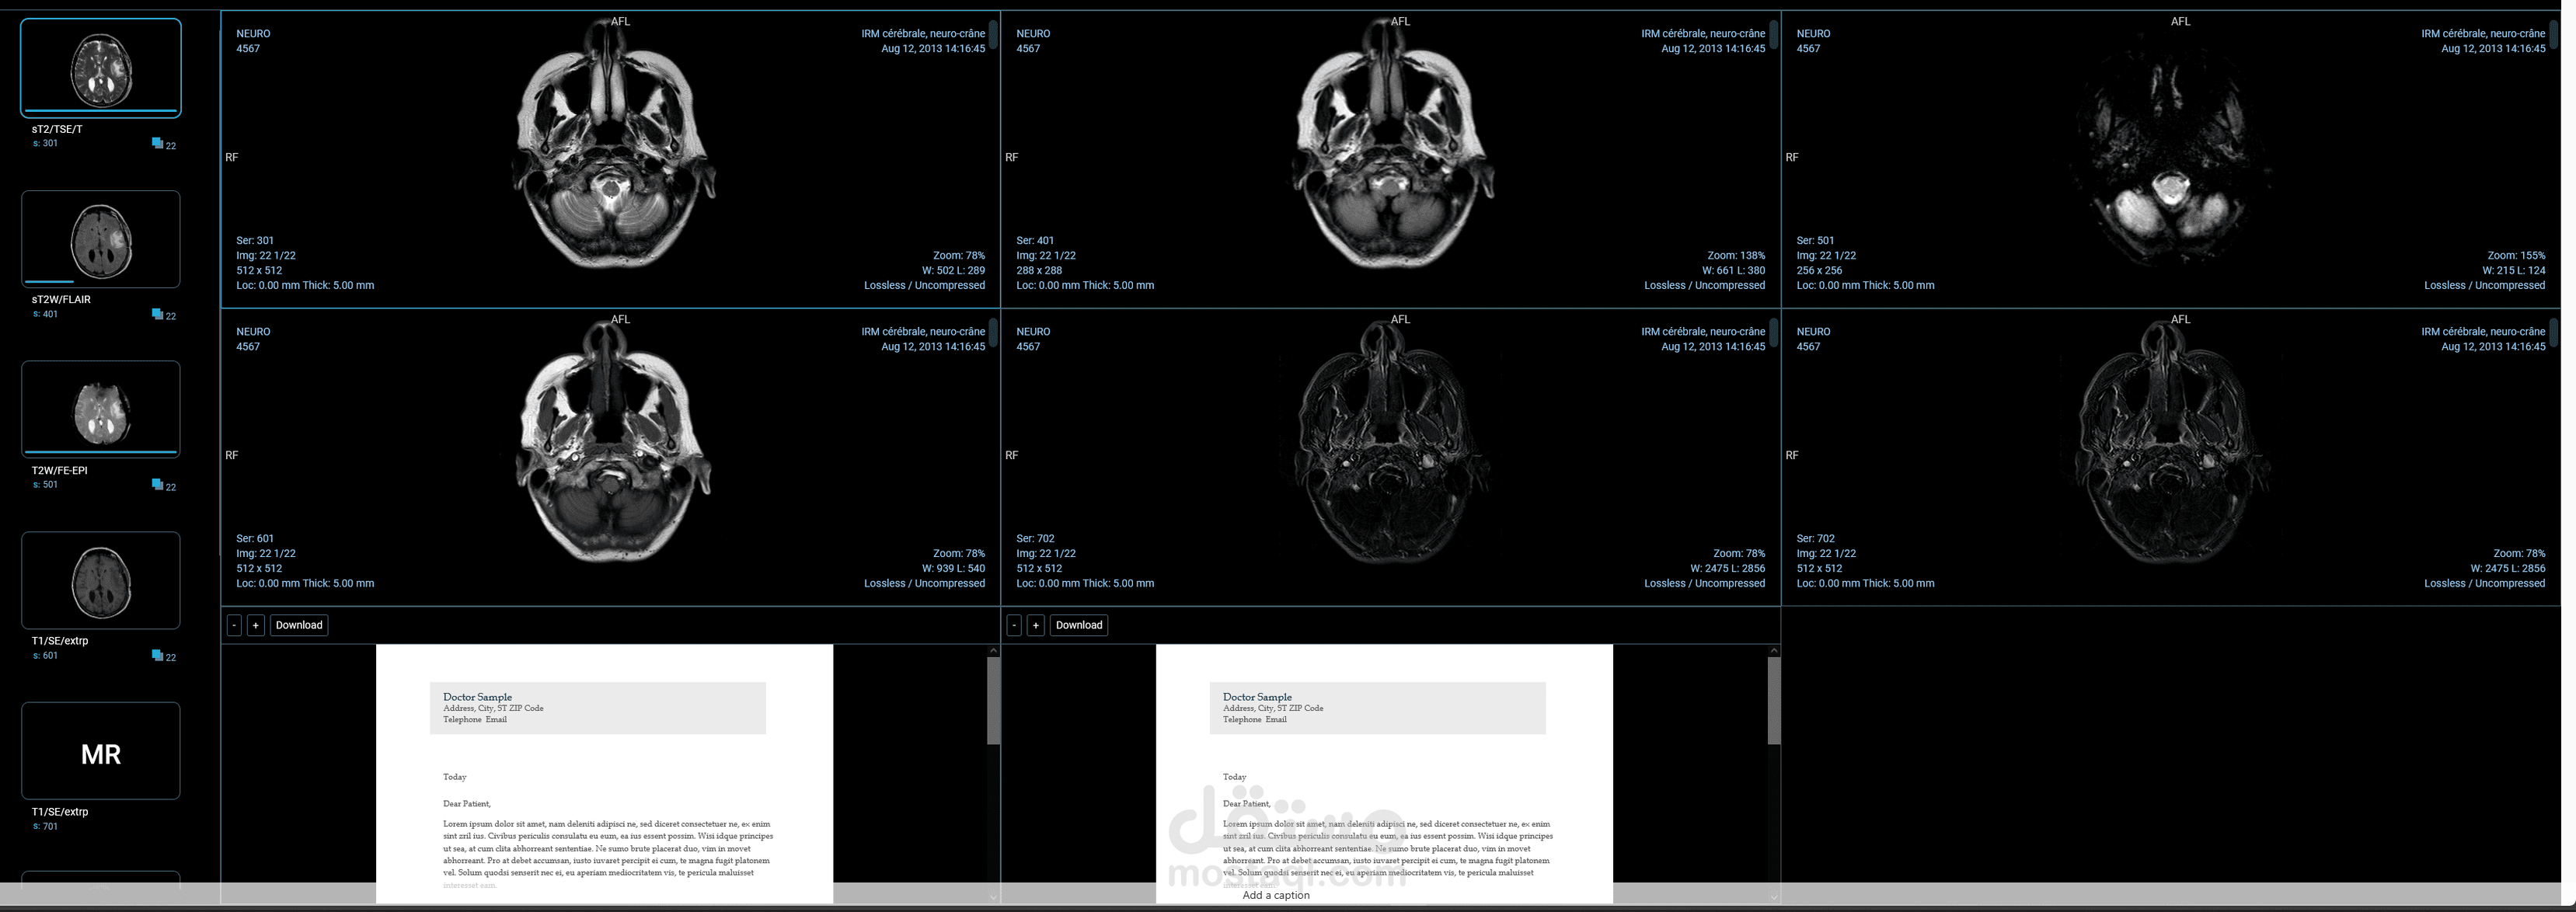

Picture archiving commendations system

نظام عبارة عن تخزين ملفات الاشعة من أجهزة : CT,MRI , XRAY الخ

وعرضها لدى الطبيب لتشخيص الحالة